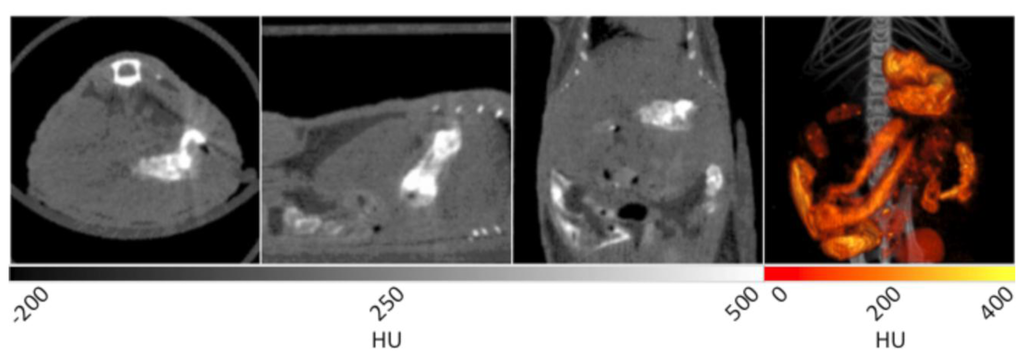

ExiTron™ was administered in daily aliquots of 25% of the recommended dose over a four-day period. This strategy was developed based on acute toxicity and mortality that was noted within our lab following the administration of a whole dose. This approach precluded imaging of the vasculature, but excellent liver and spleen contrast was observed due to high retention of the contrast agent therein. Figure 5 shows that liver tissue is greatly enhanced while fine liver vasculature may be distinguished via negative contrast.

In the transverse and sagittal planes, several lobes of the liver are enhanced while a small degree of vasculature is seen in negative contrast. In the coronal plane, a greater degree of fine vasculature can be seen in negative contrast along the periphery of the liver. It is on this bright palette that negative contrast arising from non-functional lesions may be observed as negative contrast. Spleen enhancement is also achieved to a similar degree as noted in the liver. In the 3D rendering at right, all lobes of the liver can be seen in addition to the spleen using a rainbow intensity scale generated in similar fashion to that described for vasculature. This image provides a view of the complete liver structure in three dimensions, in which gross anatomical changes may be visualized with disease progression.